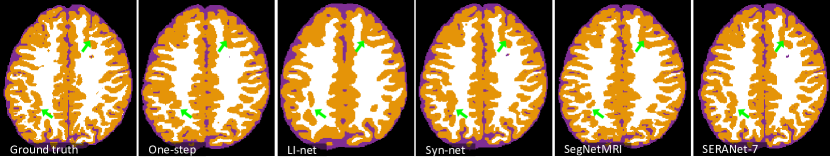

We provide qualitative and quantitative comparisons to three state-of-the-art algorithms: LI-net[10] Syn-net[10], and SegNetMRI[11]. We also compare to the One-step model. We list the performance of SERANet-7 that with 7 reconstruction blocks and SERANet-2 that with 2 reconstruction blocks. The results of all methods are reported in Table 2. We also list whether the method is pretrained and what loss the method uses to optimize in column 2 and 3, respectively. For LI-net and Syn-net, since they perform segmentation from fully-sampled data as a warm start, we consider this as a pretraining technique. We observe that SERANet-2 and SERANet-7 consistently outperform the three state-of-the-art approaches for both 10% and 20% noises. Additionally, the Diceβs scores drop more for the SegNetMRI when noise level increases compared to SERANet, which may be due to the fact that SegNetMRI contains information from the noisy ground truth images. Example segmentation results are shown in Figure 4. Improvements of SERANet-7 on detailed anatomy structure are highlighted by the green arrows.

In this section, we provide additional quantitative results. We demonstrate the comparison results of our SERANet and other approaches on data with (Figure 8) white Gaussian noise and data with noise (Figure 9). For LI-net and Syn-net, we only show their segmentation results since they bypassed the reconstruction step. For our SERANet, we present the results of SERANet-2, SERANet-4 and SERANet-7 here.